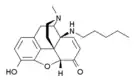

Oripavine derivatives

Thienorphine

- 7-PET

- Acetorphine

- Alletorphine (N-allyl-noretorphine)

- BU-48

- Buprenorphine

- Buprenorphine-3-glucuronide

- Cyprenorphine

- Dihydroetorphine

- Etorphine

- Homprenorphine

- 18,19-Dehydrobuprenorphine (HS-599)

- N-cyclopropylmethylnoretorphine

- Nepenthone

- Norbuprenorphine

- Norbuprenorphine-3-glucuronide

- Thevinone

- Thienorphine

Structures

| Oripavine derivatives | ||||

|---|---|---|---|---|

7-PET 7-PET |

Acetorphine Acetorphine |

Alletorphine Alletorphine |

BU-48 BU-48 |

Buprenorphine Buprenorphine |

Cyprenorphine Cyprenorphine |

Dihydroetorphine Dihydroetorphine |

Etorphine Etorphine |

Homprenorphine Homprenorphine |

18,19-Dehydrobuprenorphine 18,19-Dehydrobuprenorphine |

N-cyclopropylmethylnoretorphine N-cyclopropylmethylnoretorphine |

Nepenthone Nepenthone |

Norbuprenorphine Norbuprenorphine |

Thevinone Thevinone |

Thienorphine Thienorphine |